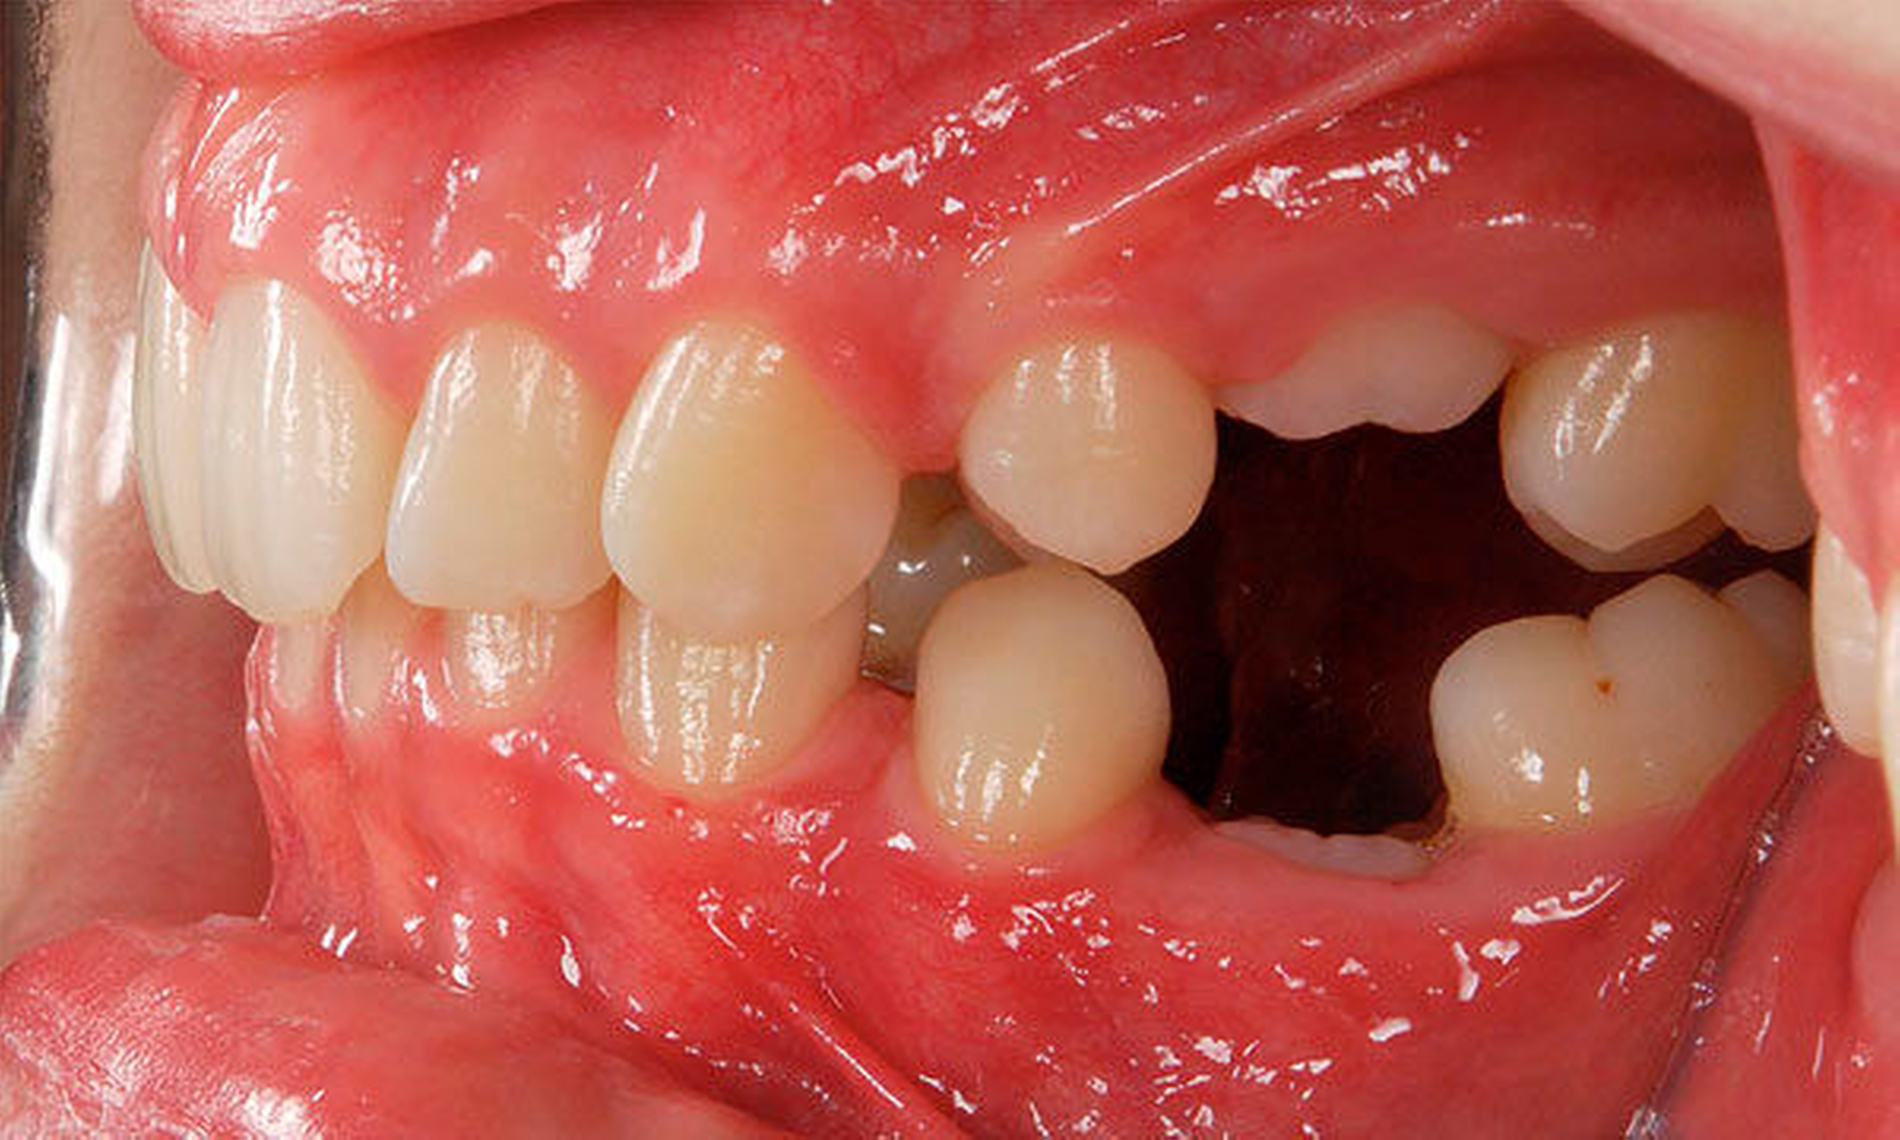

Ein zeitlich asymmetrischer Durchbruch gleichnamiger Zähne im gleichen Kiefer (Antimeren, zum Beispiel Zähne 16 und 26) kann grundsätzlich einen Hinweis auf einen gestörten Durchbruch geben. Die Abweichung von der korrekten Durchbruchsrichtung kann zu einer unterminierenden Resorption der distalen Wurzel des Milchfünfers führen. Dies wird bei circa 5 Prozent aller Kinder [van Waes, 2001] beobachtet. In ausgeprägten Fällen bleibt der Sechser an der Schmelz-Zement-Grenze oder unter der Milchzahnkrone „hängen“. Aus kinderzahnärztlich-kieferorthopädischer Sicht sollte bei solchen „Verkeilungen“ der Sechsjahrmolaren unter den teilweise anresorbierten zweiten Milchmolaren an separierende Maßnahmen gedacht werden, um den Sechsjahrmolaren aus der Verklemmung zu befreien (Abbildung 5). Ideal ist hierbei eine Aufrichtung des Sechsers nach distal, um die Stützzone möglichst wenig einzuengen. Geht der zweite Milchmolar verloren oder wird aufgrund extremer Verkeilung extrahiert, muss in der Regel später kieferorthopädisch der Platz für den bleibenden zweiten Prämolaren wiederhergestellt werden, da der Sechser mesialwärts durchbricht (Abbildung 6).